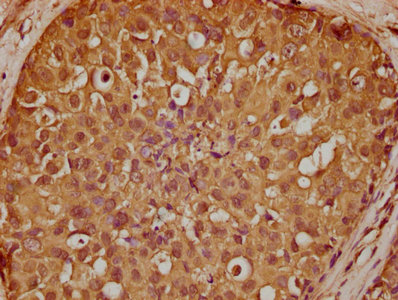

IHC image of CSB-PA020731LA01HU diluted at 1:200 and staining in paraffin-embedded human breast cancer performed on a Leica BondTM system. After dewaxing and hydration, antigen retrieval was mediated by high pressure in a citrate buffer (pH 6.0). Section was blocked with 10% normal goat serum 30min at RT. Then primary antibody (1% BSA) was incubated at 4°C overnight. The primary is detected by a biotinylated secondary antibody and visualized using an HRP conjugated SP system.